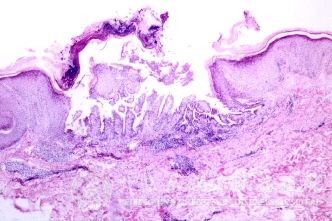

北京京城皮肤医院指出,紫外线性皮炎的发病机制:阳光中紫外线骤增会损伤皮肤表皮*,使蛋白质发生变性分解、毛细血管扩张充血,从而导致皮炎。